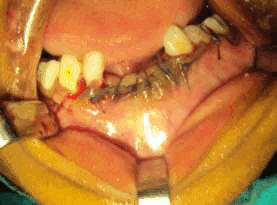

Рис. 4. На интраоперационной фотографии образование захватывает зубные зачатки 41 и 42 зубов.

Рис. 5. На фотографии до операции видно, что образование распространяется от медиальной части 83 до медиальной части 74.

Впоследствии пациентке был выполнен кюретаж образования под общим наркозом. Для предотвращения образования гематомы был наложен узловой шов. Состояние пациентки после операции удовлетворительное. Послеоперационный период протекал без осложнений, на 3 день пациентка была выписана.

Рис. 7. Наложение послеоперационного шва викрилом.